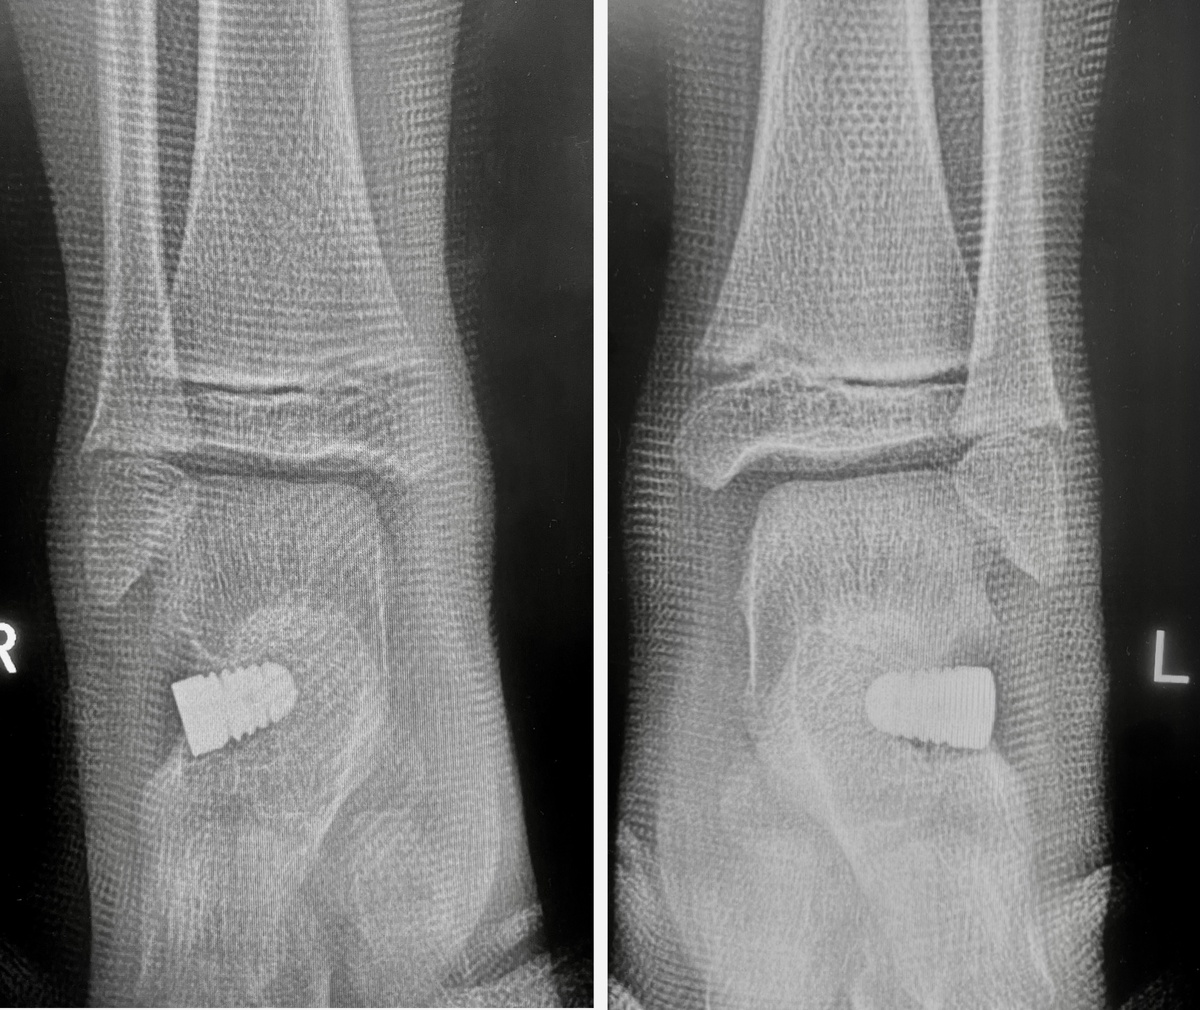

Написать этот пост сегодня меня сподвиг визит здоровенного верзилы — под 90 кг и ростом 185 см, с размером стопы 45 в 15 лет!! Оперировал я его в 2018 году в возрасте 8 лет. Тогда он пришёл с мамой за ручку вот с такими «лежащими» сводами и заваленными пятками:

Обошлось максимально простой хирургией:

Вот такими двумя имплантами (одновременно). Прошло 7 лет, картина вот такая: